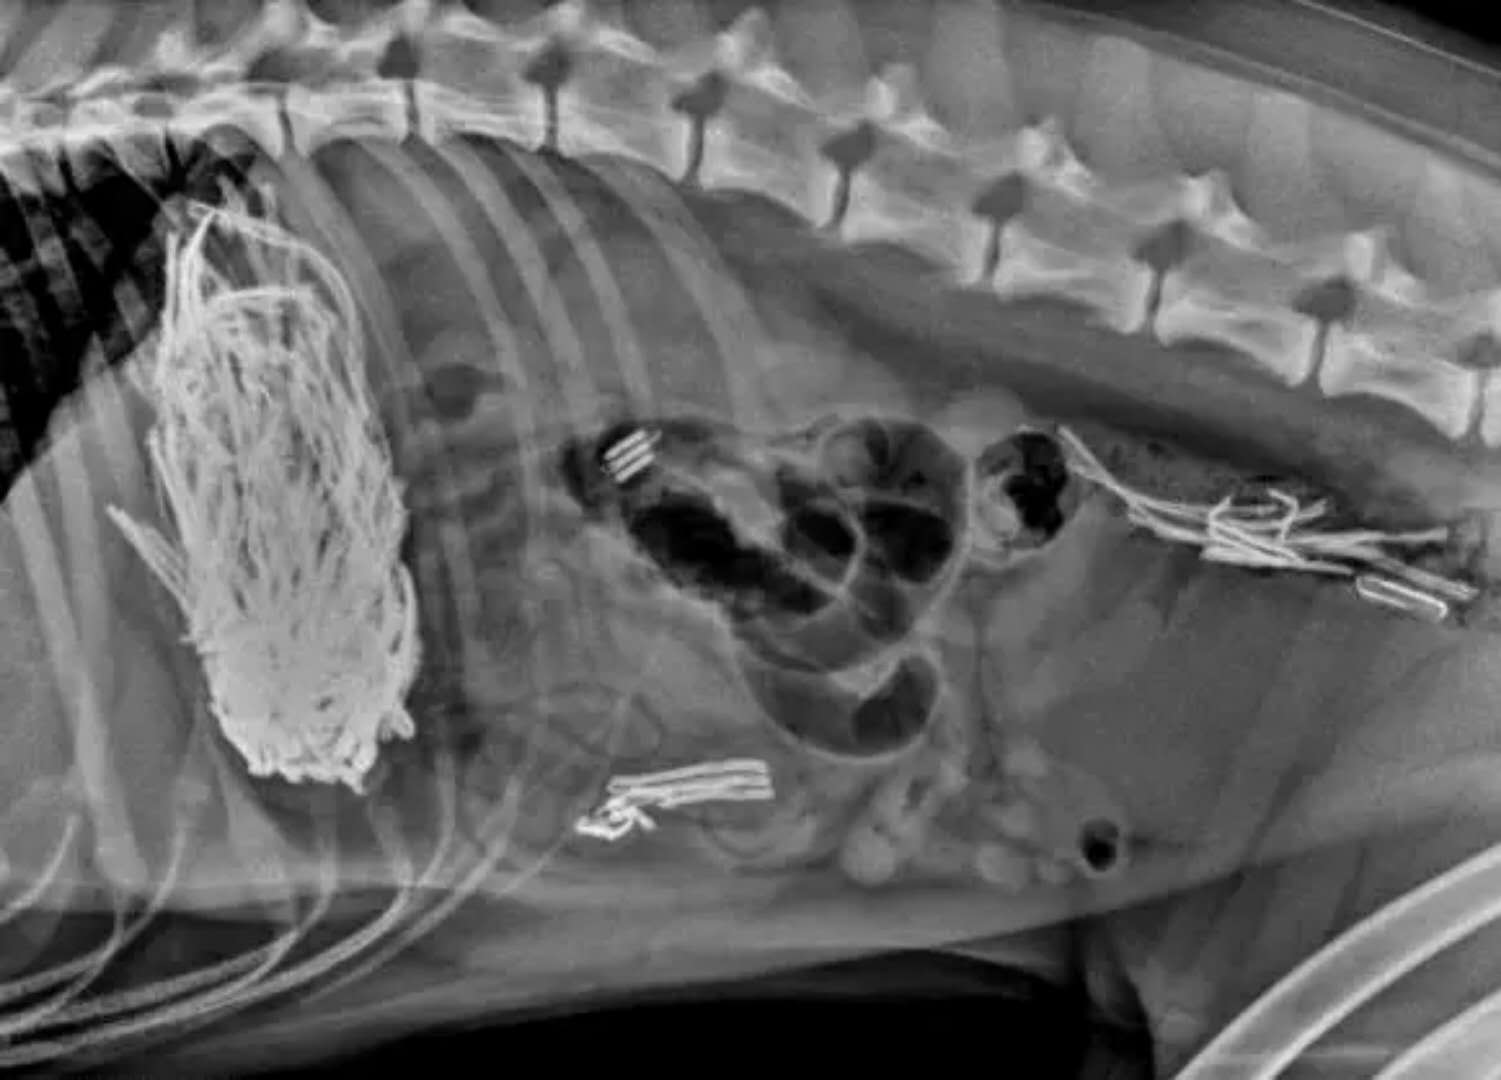

这是小孩的玩具车

这些都是在狗狗的胃里发现的,拍的X光图,看到那把刀在狗狗胃里,心里不紧张吗不担心 ,万一你家的狗狗也吃下去,想都不敢想!

狗狗似乎总是无法控制自己去吃一些没有营养价值的东西。针线、木勺、硬果壳、果核、塑料袋、珠宝、石块、抹布和袜子都有可能吃下去,狗狗胃内长期滞留这些异物不能被胃液消化,会造成胃黏膜损伤,影响胃功能。